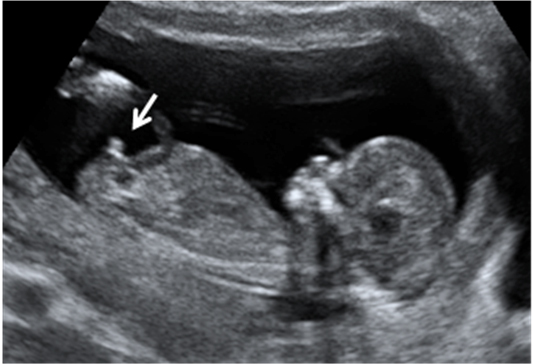

En la ecografía de la semana 12 de embarazo se distingue los genitales del feto, lo que permite saber con bastante probabilidad de acierto si se trata de una niña o un niño, como en este caso.

Cómo se ven los genitales de un feto varón de 12 semanas en la ecografía

Vemos en esta ecografía en dos dimensiones de un feto de 12 semanas. Si nos fijamos en la flecha, el tubérculo genital apunta hacia delante, lo que hace muy probable que el feto sea de sexo varón.